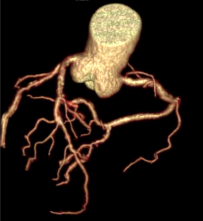

Công nghệ tim mạch Aheart

Khám phá nhiều hơn, đi sâu vào từng chi tiết

Hình ảnh lâm sàng